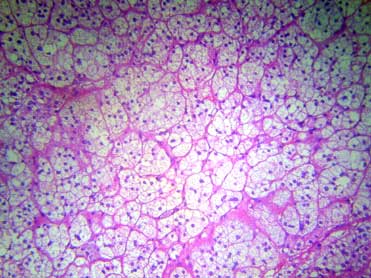

Hình ảnh xốp bào, nhân hỏ lệch tâm, bào tương chứa đầy mỡ